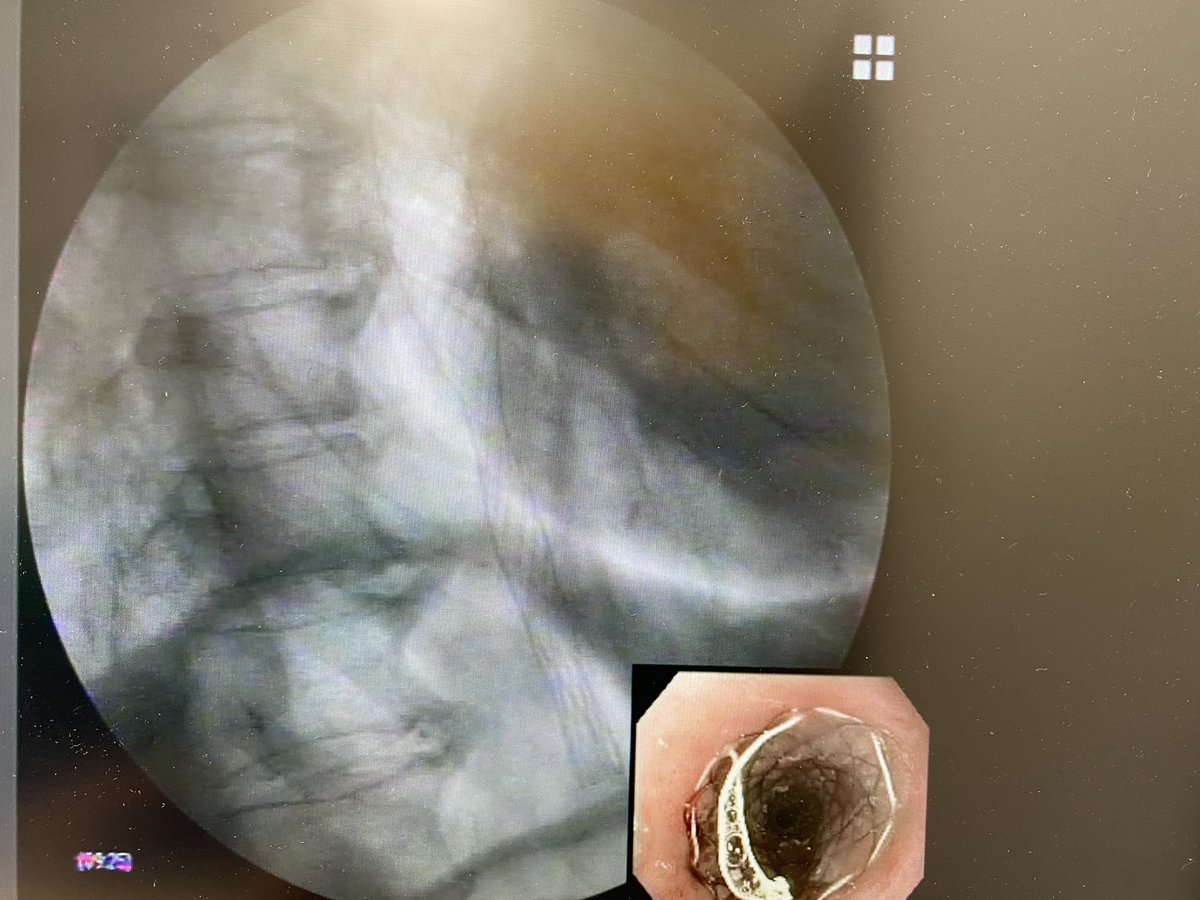

Últimos pasitos de la mano de Alicia Brotons y Javier Sola-Vera… prótesis de esófago parcialmente recubierta en estenosis maligna ✌️✔️ #womeninendoscopy #HGUE

Últimos pasitos de la mano de <a href="/abbwonderland/">Alicia Brotons</a> y Javier Sola-Vera… prótesis de esófago parcialmente recubierta en estenosis maligna ✌️✔️

#womeninendoscopy #HGUE